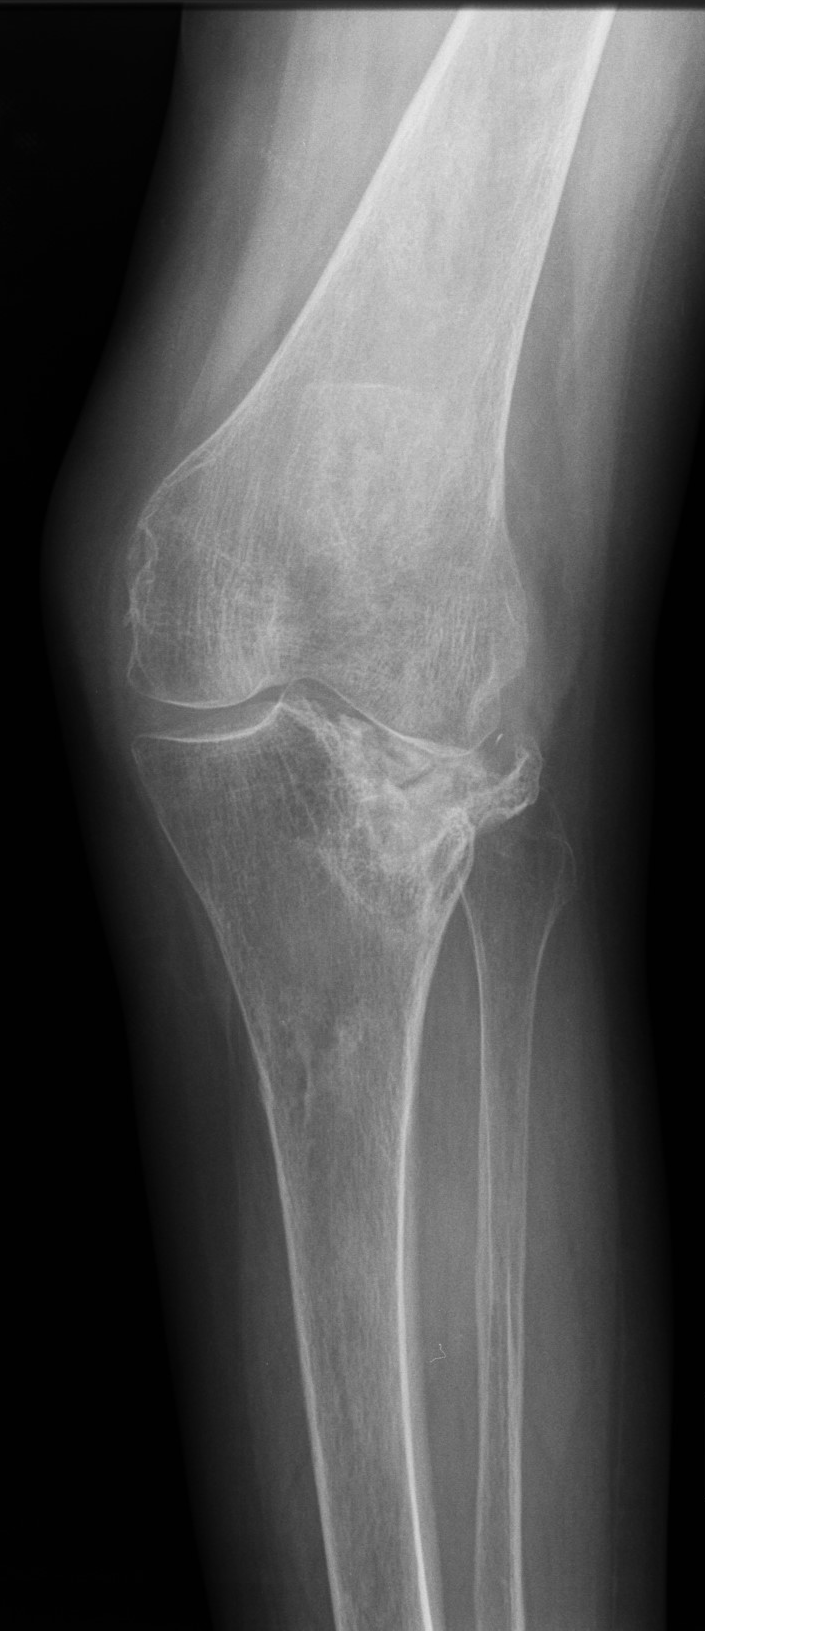

- Ендопротезиране на колянна и тазобедрена става

Основно лекувам заболявания на тазобедрена и колянна става чрез минимално инвазивно ендопротезиране, следтравматични и дегенеративни нарушения на ръката и китката и халукс валгус (популярен като „кокалчета на краката”).